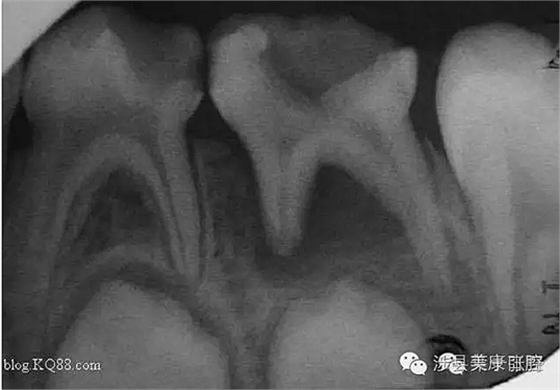

普通家長看了這張牙片估計能看出來孩子的牙不好,但是究竟不好到什么程度呢,讓葉子姐告訴大家:

上圖孩子的乳牙感染已經(jīng)將下面骨感染到吸收消失,并且直接影響到了下面的恒牙胚,家長們上點心吧。那些說乳牙不用治療,換牙就會好的人(包括醫(yī)生)還是睜開眼睛看看吧,不要自欺欺人,更不要用自己的錯誤誤導(dǎo)他人誤導(dǎo)大眾。

網(wǎng)友又不明白了,什么叫吸收消失?看x片看不懂哎......

黑色部分表示那里的骨頭感染已經(jīng)爛沒有了,消失了,牙胚應(yīng)該在健康頜骨里孕育生長發(fā)育,現(xiàn)在在感染的病灶里生長,在膿水里侵泡。

又有好奇網(wǎng)友問他怎么有那么多牙?

乳牙下面有恒牙孕育著。